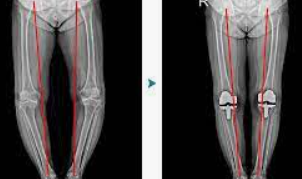

인공 관절 수술은 퇴행성 관절염이나 다른 관절 손상으로 인해 자연 관절이 기능을 상실했을 때 고려되는 치료 방법입니다. 이 수술은 손상된 관절을 인공 재료로 만든 새로운 관절로 교체하는 과정을 포함합니다. 수술 비용은 다양한 요인에 따라 달라질 수 있으며, 환자의 나이, 수술의 복잡성, 사용되는 재료의 종류, 병원의 위치와 수준 등에 따라 천차만별입니다. 일반적으로, 수술 비용은 수술 전 검사비, 수술비, 입원비 등을 포함하여 수백만 원에서 천만 원 이상이 될 수 있습니다. 또한, 환자의 건강보험 적용 여부에 따라 실제 환자가 부담해야 하는 비용은 크게 달라질 수 있습니다. 건강보험 적용을 받을 수 있는 경우, 환자의 부담금은 상당히 줄어들 수 있으며, 특정 조건을 충족하는 경우 추가적인 정부 지원을 받을 수도 있습니다. 수술 후에는 일정 기간 동안 재활 치료가 필요할 수 있으며, 이는 전체 치료 비용에 영향을 미칠 수 있습니다. 인공 관절 수술은 환자의 삶의 질을 향상시킬 수 있는 중요한 수단이 될 수 있지만, 수술을 결정하기 전에 비용과 잠재적인 결과에 대해 의료 전문가와 상세히 상담하는 것이 중요합니다.

인공 관절 수술은 관절의 퇴행성 변화, 외상, 또는 다른 질환으로 인해 손상된 관절을 인공적인 재료로 만든 관절로 교체하는 의료 절차입니다. 이 수술은 주로 무릎, 고관절, 어깨 관절 등에 적용되며, 환자의 삶의 질을 향상시키고 통증을 감소시키는 데 목적이 있습니다.

최근에는 로봇 인공관절 수술이 도입되어, 수술 과정에서 발생할 수 있는 정상 조직의 손상과 출혈을 최소화하고, 수술 부위를 신속하고 정확하게 절개할 수 있어 회복이 빠르고 재활이 용이해졌습니다.